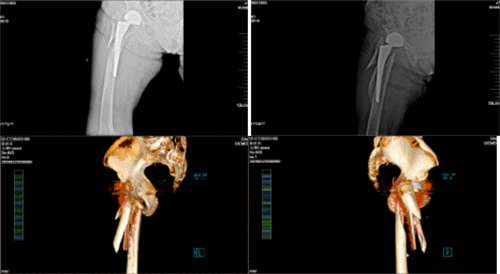

(术前检查提示假体周围骨折)

(术后X线提示新植入假体位置良好)